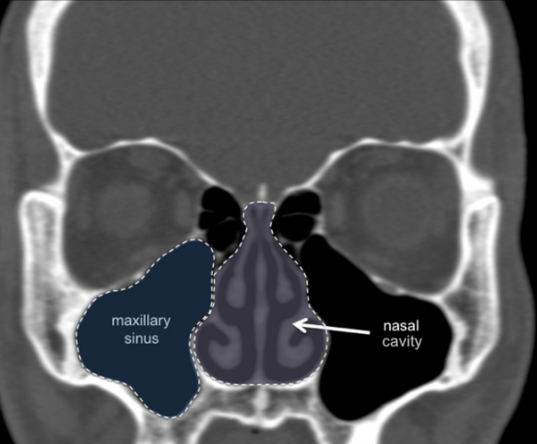

- Apico-coronal positioning:

- Place bone-level implants 2-3mm subcrestally in the esthetic zone

- Adjust depth based on implant system recommendations

- Consider soft tissue thickness for proper emergence profile development

- Implant angulation:

- Maintain angulation within 0-15 degrees of ideal axis to minimize off-axis forces

- Align implant with prosthetic requirements for screw-retained restorations

- Avoid extreme angulations that necessitate custom abutments